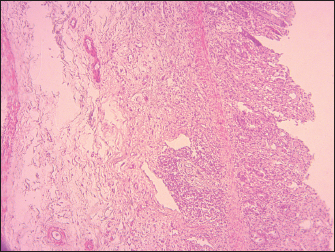

The most important histopathological lesions were observed in the lungs, intestines, spleen, and lymph nodes. The lungs had the most severe histopathological abnormalities, which were characterized by edema in the alveoli combined with fibrinous exudate infiltration of mononuclear cells and thickening of the interalveolar septa (Fig. 5), presence of syncytial cells (Fig. 5). Intestines revealed ulcerations of the intestinal mucosa in some areas, loss of intestinal villi with the intestinal crypts appearing clear and loss of epithelium, the lamina propria was infiltrated with Macrophages and lymphocytes, the duodenum, jejunum, and ileum showed extensive effusion of the submucosa with progressive thickening of the submucosal layer (Fig. 6). Degeneration and necrosis of glandular epithelial cells were also seen.

Fig. 6. Sheep, small intestine mucosa showing total loss of villi, ulceration, and inflammatory cell infiltration, thickening of submucosa by edema. Moderate depletion of Peyer’s patches (100X, H&E).

In the intestine, particularly the ileum and colon, there was evidence of marked hemorrhagic and necrotic changes. The atrophy of intestinal villi could be attributed to the epitheliotropic characteristics of the PPRV (Maina et al., 2015) causing necrosis of epithelial cells. These lesions are a principal factor in the clinical presentation of severe muco-hemorrhagic diarrhea. The histopathological lesions of the intestine in the current study are in correlation with those reported by Begum et al. (2021) and Patel et al. (2017).